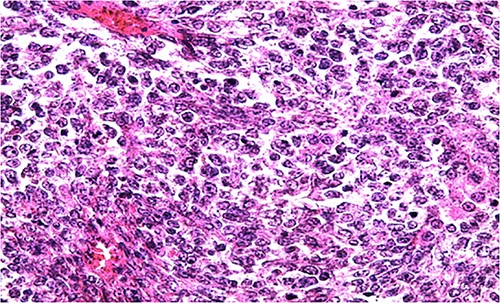

Biologically, the CA 125 tumor marker was at 126.2 IU/ml. The patient underwent a left adnexectomy and an omentectomy (small omentum). Macroscopically, the ovarian mass was smooth on the surface and fleshy on section with the presence of necrotic and hemorrhagic changes. On the histological level, the tumoral proliferation presents a diffuse architecture formed by sheets and clusters separated by fine fibrous septa. Tumor cells are rounded, small, and monomorphic with hyperchromatic, finely nucleolated nuclei and reduced cytoplasm. Mitotic activity is high (36 mitoses/10 HPF) (Figs 3 and 4). The samples taken from the small omentum were tumorous. An immunohistochemical study was carried out and showed diffuse positive expression by tumor cells of Vimentin, and focal by antibodies (Cytokeratin AE1/AE3, EMA, CD99, WT1, Inhibin, and SALL4) and an absence of expression by antibodies (CD45, Chromogranin, PAX8, and AFP) (Figs 5–7).

HE section of small monomorphic tumor cells showing hyperchromasia and mitotic figures (x400).